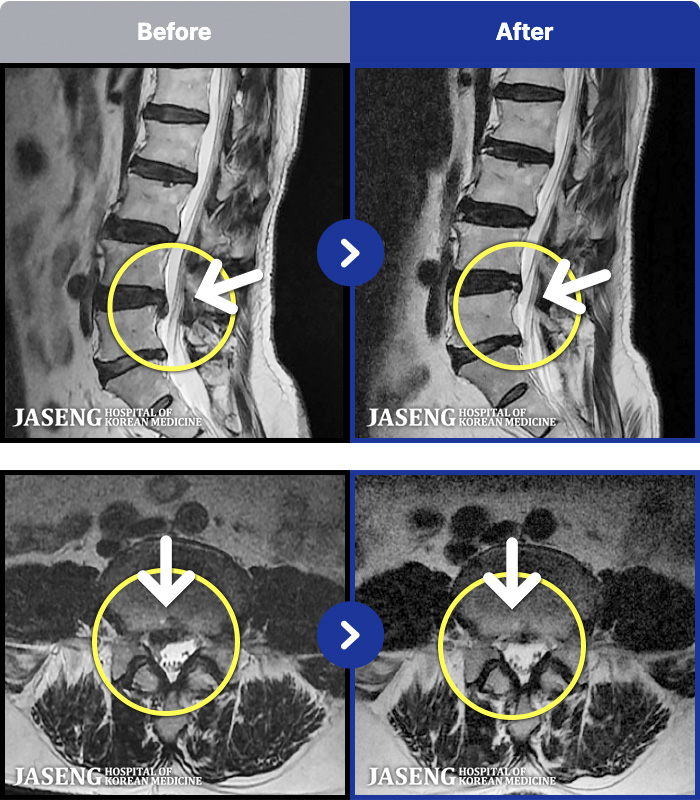

129 MRI ũ ʸ Ȯϼ.

ȯںп Ǹ ǿ ԿǾ, ο ġ ۿ Ƿ ġḦ Ͻñ ٶϴ.